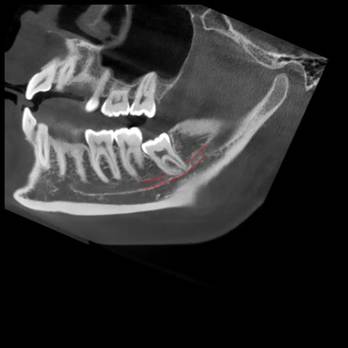

Перед любым лечением мы делаем КТ-снимок челюсти. Дальше в работу включается программа Diagnocat, которая превращает его в детализированную 3D-модель.

Так мы видим нервы, каналы, сложные изгибы челюсти, которые можно не заметить на обычном снимке. На экране можно буквально убрать нижнюю челюсть и посмотреть, как нерв проходит между корнями зуба или где он оказывается особенно близко к потенциально проблемному участку.

Если видим такую картину, например, сразу объясняем, что зуб находится в опасной близости к нерву и обычное удаление может быть рискованным.

Спустя примерно четыре недели делается повторный КТ-снимок или другой рентген. Врач делает небольшой надрез, удаляет мини-винт, а затем — сам зуб.

До и после экструзии:

И ещё одно до и после: